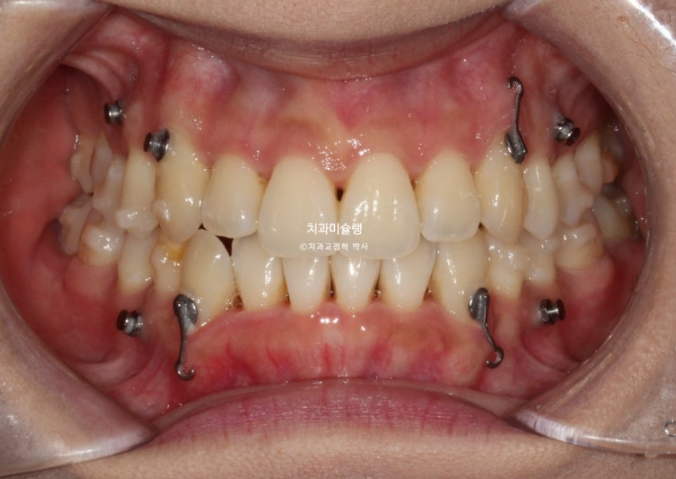

2년 전 덧니 교정치료를 위해 내원한 환자분입니다.

중심선 문제, 블랙트라이앵글, 과개교합, 반대교합, 가위교합 등이 보입니다.

발견되는 부정교합의 종류들을 나열해보자면

중심선 불일치

과개교합

대구치 가위교합

심한 덧니

전치부 반대교합

부정교합은 아니지만 블랙트라이앵글

정도가 되겠습니다.

이 정도라면 작은어금니 4개 발치교정 진단을 할만도 하지만

입술 돌출이 없고 입술이 얇아 발치교정이 고민되는 상황입니다.

결국 환자분과 논의 후 입매 변화 없는 비발치로 진행하기로 합니다.